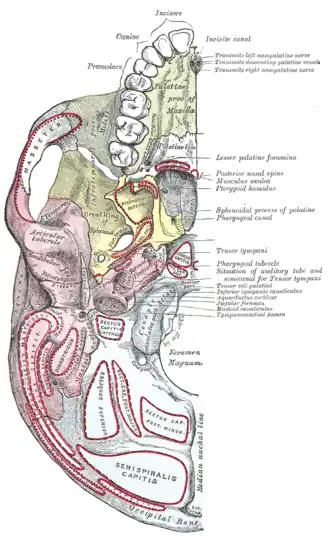

Base of skull. Inferior surface.

Base of skull. Inferior surface.